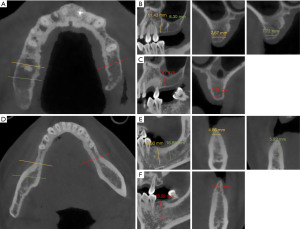

A 27-year-old woman with a childhood history of poliomyelitis presents at the Affiliated Stomatological Hospital of Zhejiang University. She understands sample instructions but cannot clearly express needs, has multiple caries-induced missing teeth affecting eating, and seeks chewing function restoration. The patient exhibits facial asymmetry, deviated mouth corners, and leftward mandibular movement on opening. She also displays asymmetric paralysis, muscle atrophy, and joint deformities (Figure 1). Intraoral examination discloses dentition defects of both arches (#16, #17, #12, #24, #26, #27, #36, #37, #46, #47) (Figure 2). Preoperative cone-beam computed tomography (CBCT) imaging indicates inadequate height of the maxillary alveolar bone (about 8 mm), with adequate quantity of the mandibular bone (Figure 3).

The entire surgical procedure is completed within 90 minutes, and the postoperative CBCT scan indicates proper implant positioning without damage to critical structures (Figure 4). The mesiodistal distances are adequate, all measuring over 1.5 cm; however, the buccolingual bone plate width is suboptimal, ranging from 1.2 to 2 cm, possibly influenced by artifacts from the implant. No significant complications were noted during and after the procedure. Six months postoperatively, the patient returns for follow-up and undergoes second-stage surgery. The implant site shows excellent healing. After removing the cover screws, healing abutments are placed (Figure 5). The digital scan is performed to create a three-dimensional (3D) model due to the patient’s poor cooperation with traditional impressions (Figure 6). A monolithic zirconia crown, known for its high elastic modulus and biomedical compatibility, is selected. Given the patient’s limited inter-arch space, the neck design is extended subgingivally, with grooves added to the sandblasted abutment surface. On the patient’s right side, a conservative occlusal design is implemented to mitigate occlusal forces. This involves the maintenance of a residual gap between #36 and #38, in addition to a reduction of the apical bevel slope and crowns for #36 and #46. The patient’s response to the restoration is carefully monitored. Once confirmed in position, the screw access holes are sealed, completing the permanent restoration (Figure 5). The patient and family are instructed on hygiene practices to maintain proper oral hygiene and advised to return for regular follow-ups. At the 4-month follow-up, the oral examination shows secure implant retaining screws. Peri-implant soft tissues exhibit favorable morphology, and occlusal relationships remain consistent (Figure 7). The family reports significant improvement in masticatory function, with no abnormal reactions to daily foods.